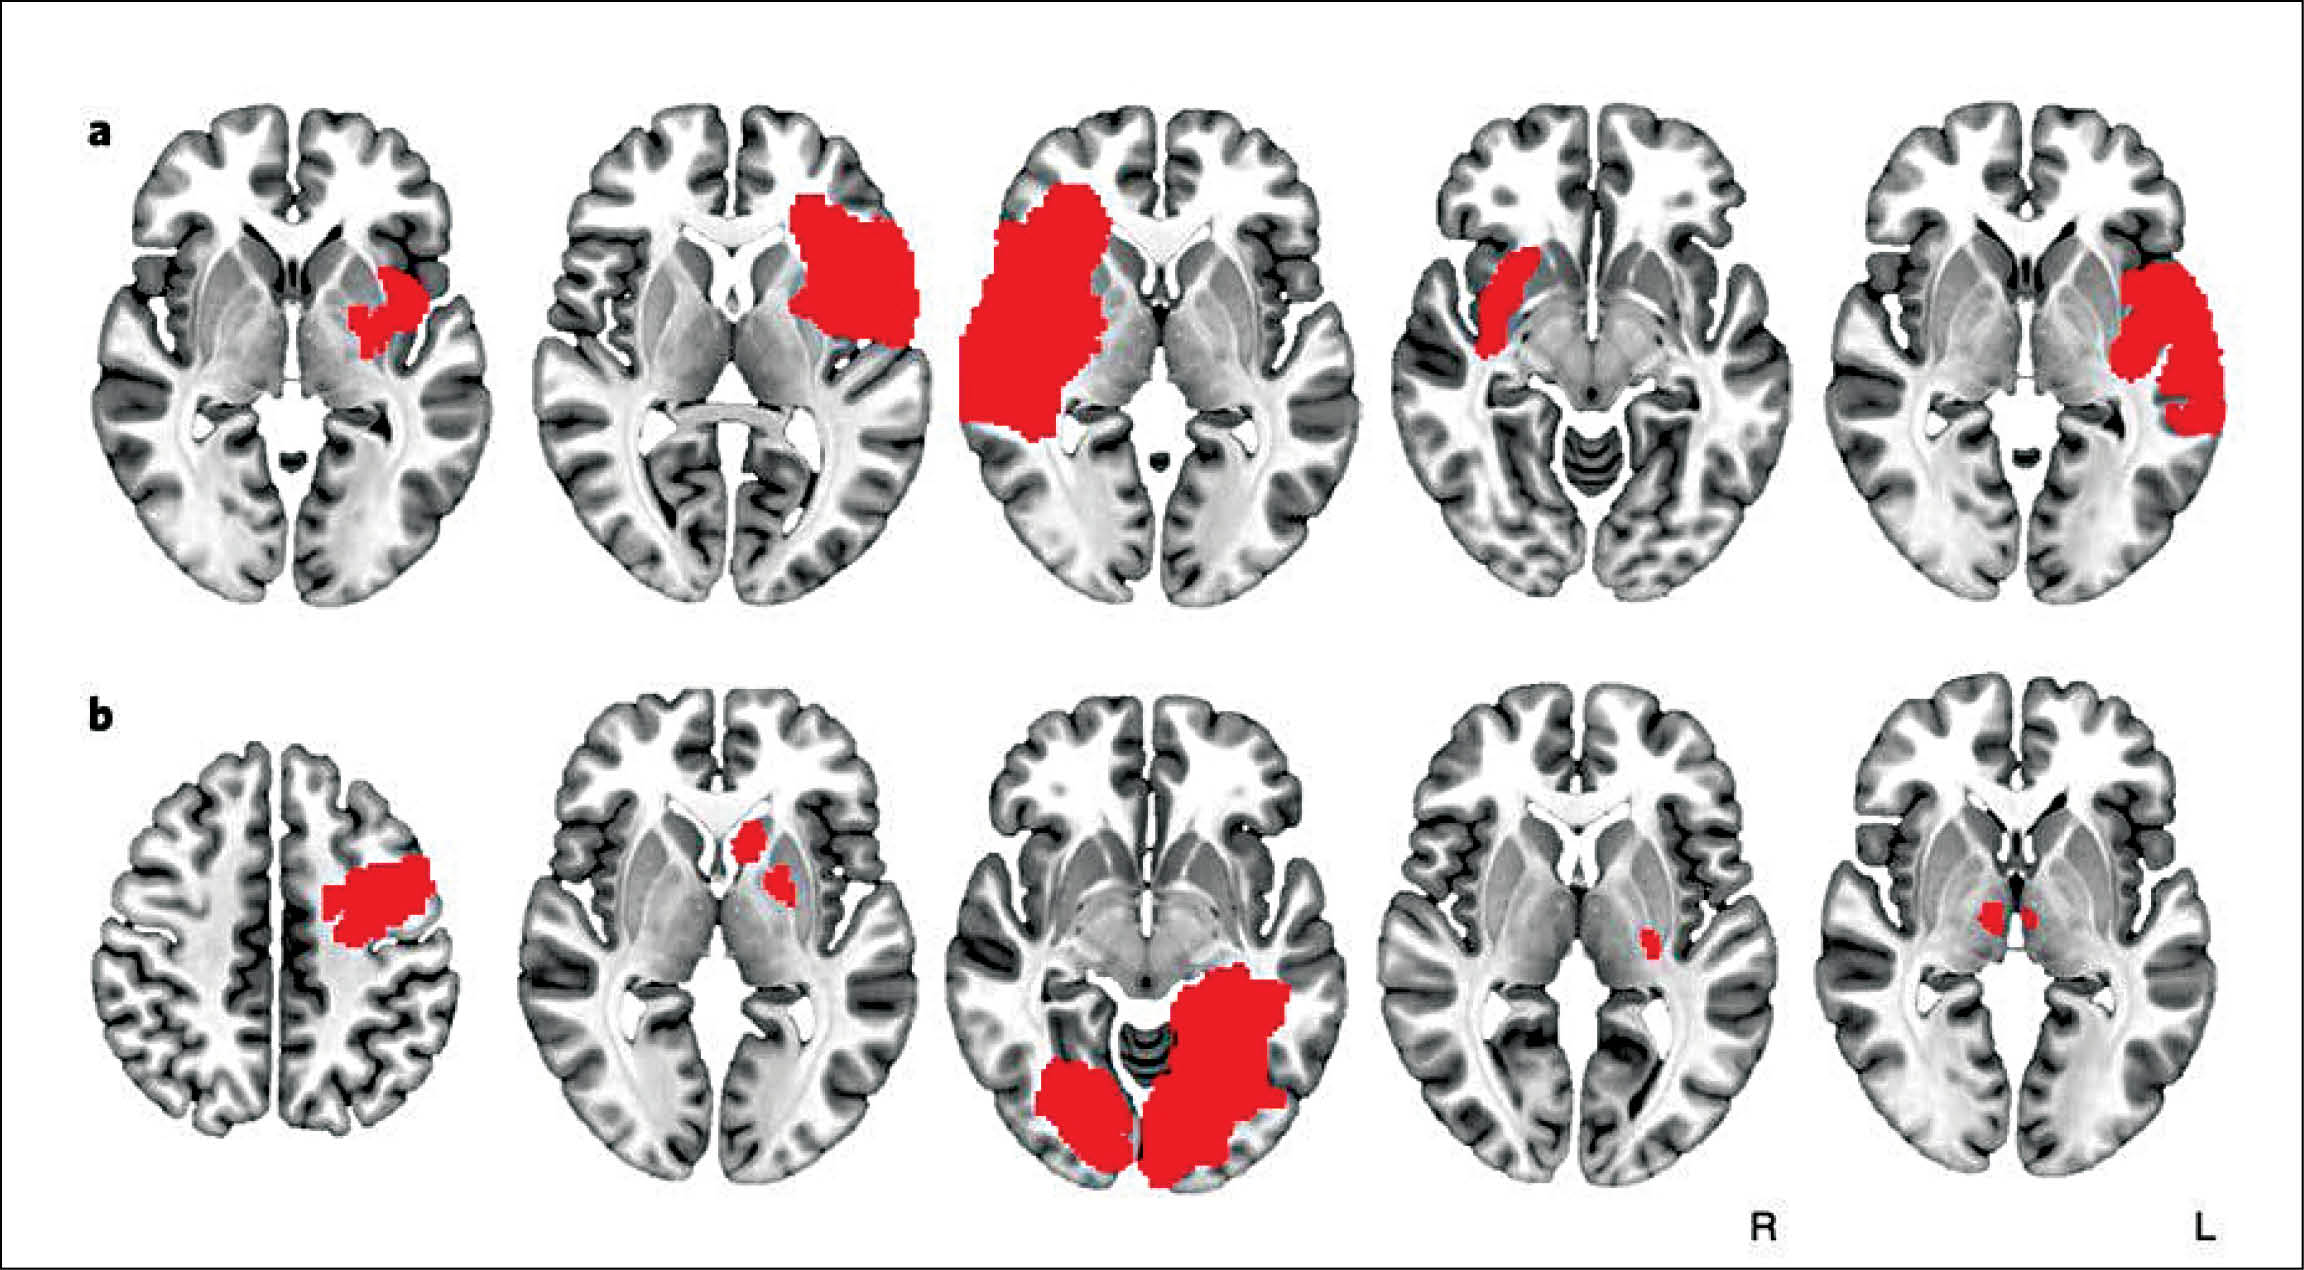

اسکن مغز آسیبدیده اغلب نقشهای از صدمات غیرقابلجبران و نقاطی که آسیب باعث مشکلات حافظه یا لرزش اندامها میشود را به متخصص نشان میدهد.